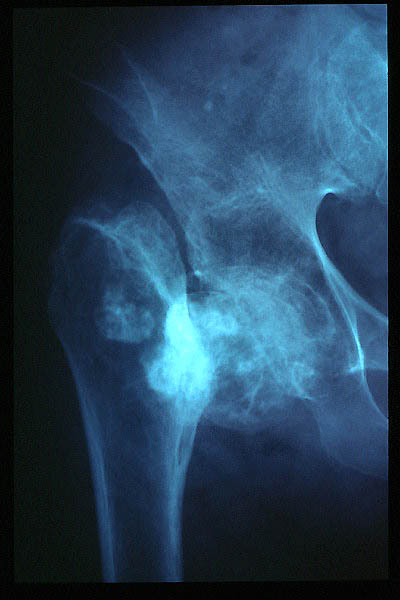

E de Paget

Artrosis avanzada de cadera. Anquilosis.

Artrosis anquilosante de cadera.

Atrosis avanzada de cadera.